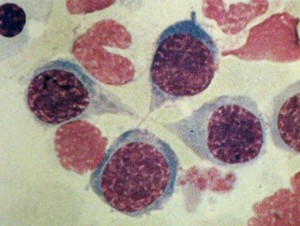

Mitose em células de aspirado de medula óssea

Principais achados de mitose em aspirados de medula óssea.

Telófase completa (quatro células filhas, normoblastos basófilos)